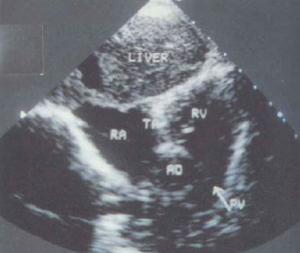

(5)M型超聲心動圖顯示三尖瓣雙峰曲線消失,四腔切面檢查未能見到三尖瓣回聲反射,房間隔回聲中斷,並有心室間隔上部回聲中斷。超聲心動圖和都卜勒檢查並可見到血流自右房至左心房再進入左室。二尖瓣活動幅度增大,右房、左房、左室腔均增大,右心室小或消失。